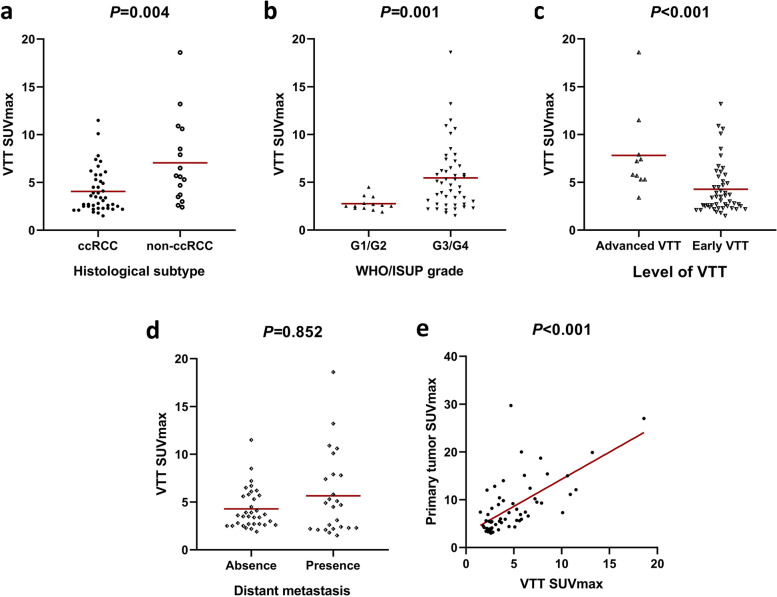

Correlations of VTT SUVmax with clinicopathological characteristics and other PET/CT parameters

As presented in Fig. 3, VTT SUVmax was markedly higher in patients with non-ccRCC (P = 0.004), WHO/ISUP grade 3/4 (P = 0.001), and advanced VTT (P < 0.001), but had no remarkable difference between the metastasis and non-metastasis groups (P = 0.852). A significant linear correlation was found between VTT SUVmax and primary tumor SUVmax (P < 0.001, r = 0.667).

Fig. 3.

Comparisons of VTT SUVmax between subtypes of histological subtype (a), WHO/ISUP grade (b), level of VTT (c) and distant metastasis (d), and correlation with primary tumor SUVmax (e), respectively